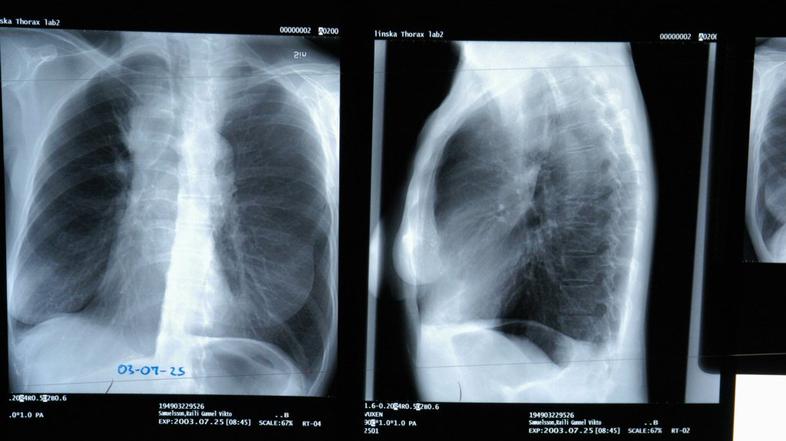

Pljučni rak Profimedias